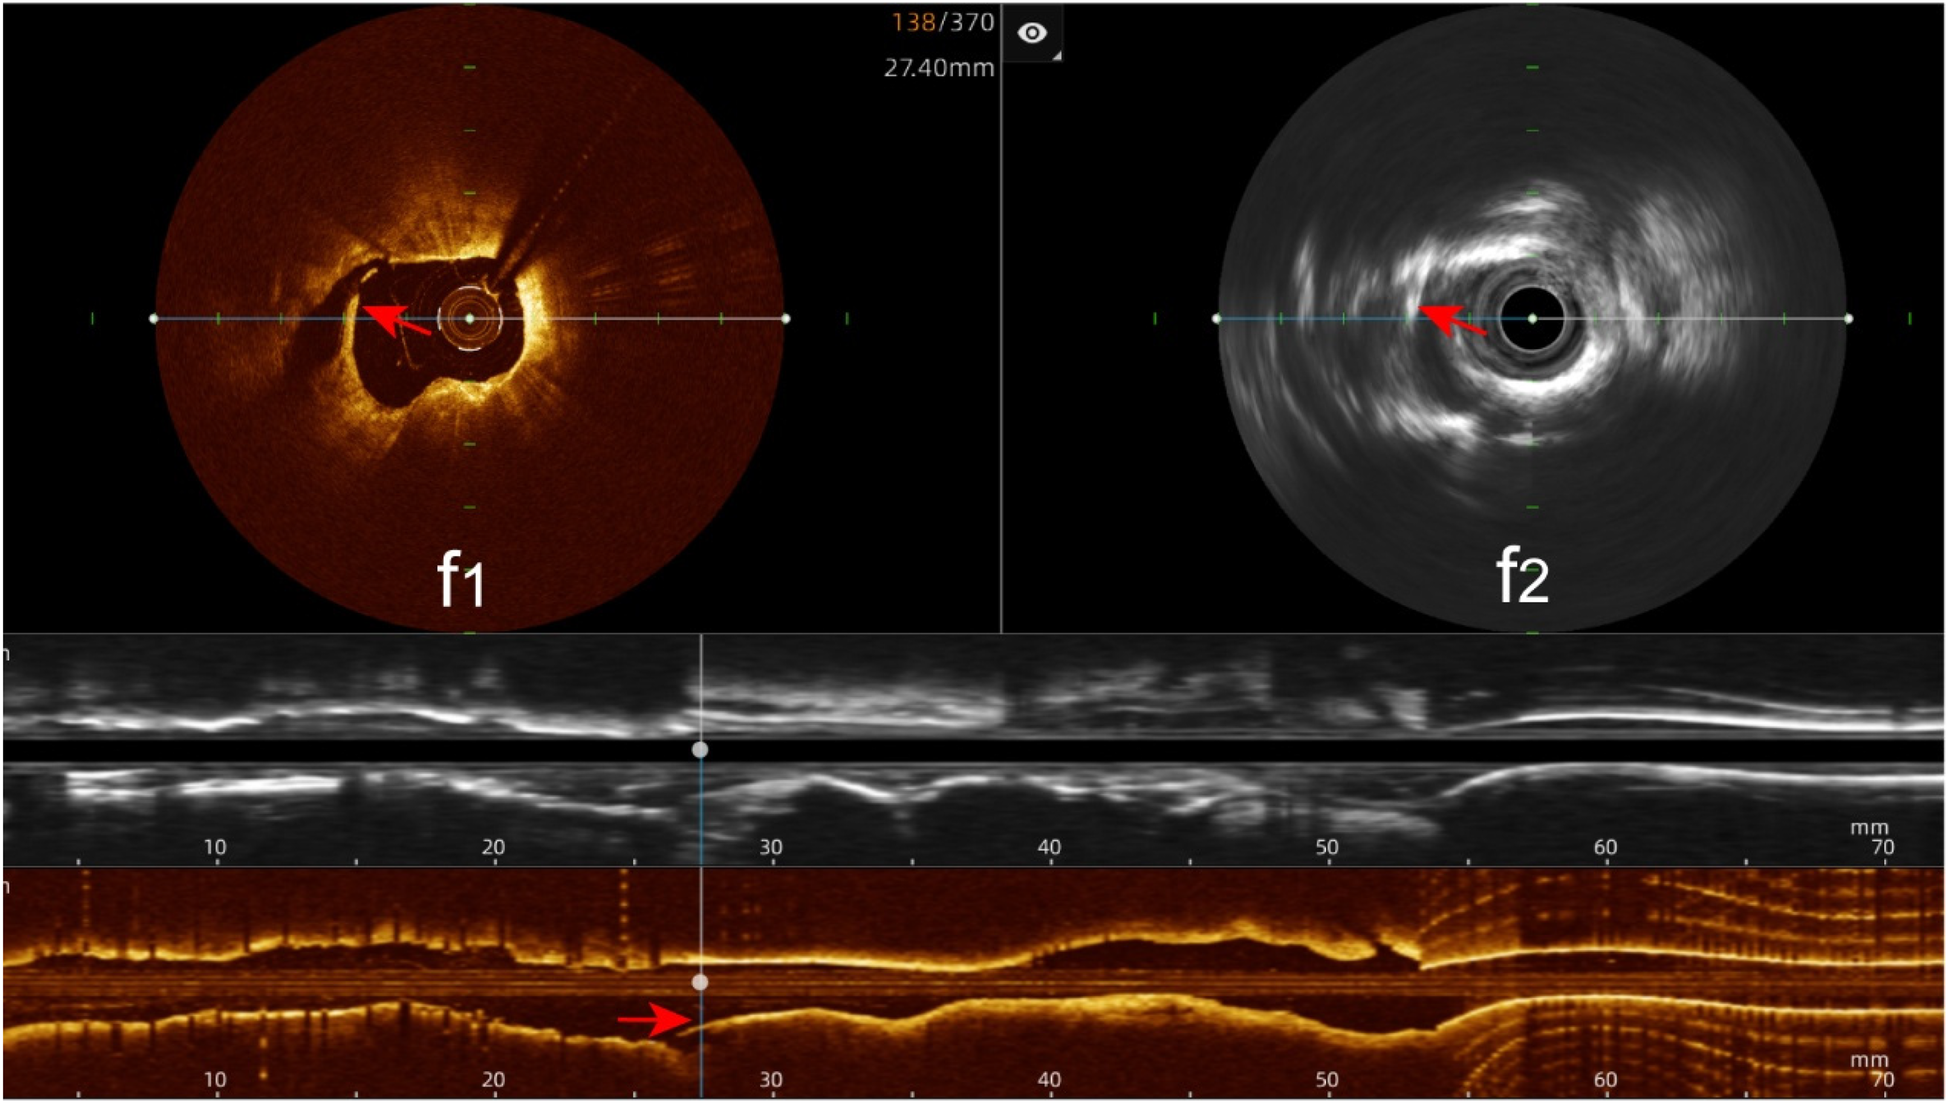

Stent edge dissection: The hybrid IVUS-OCT imaging system identified 10 cases of stent edge dissection, compared with OCT detecting 10 (100%) and IVUS detecting 7 (70%) (P = 0.211;Figure 11;Table 3;Figure 8).

Figure 11

Immediate evaluation of the hybrid IVUS-OCT images after coronary stenting (stent edge dissection). (f1,f2) OCT and IVUS clearly show stent edge dissection.